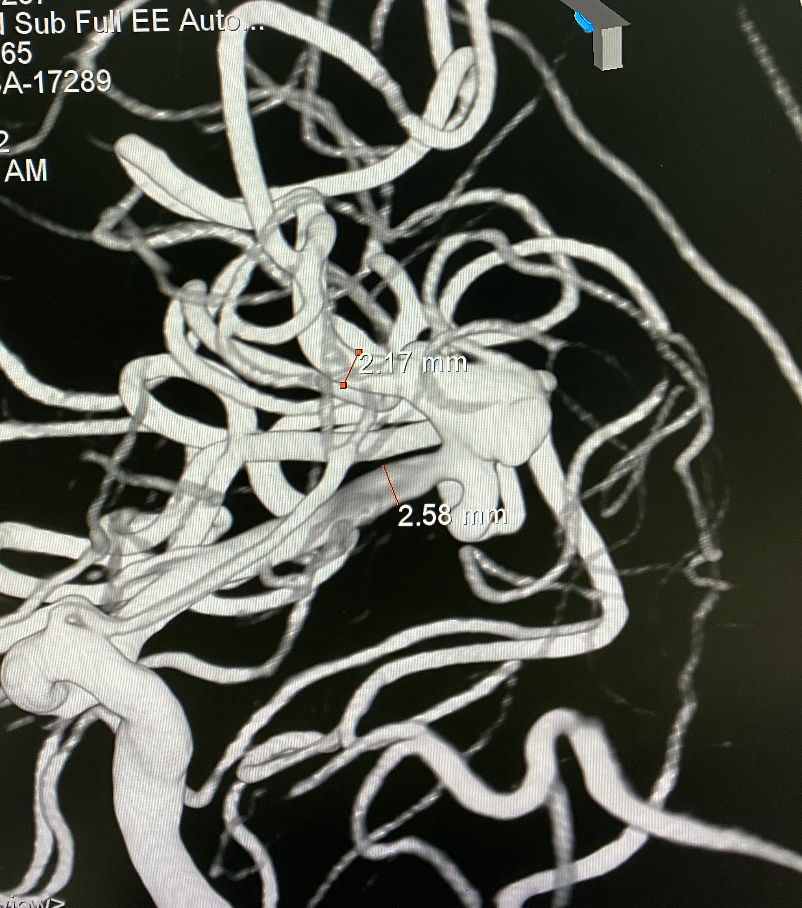

远近端载瘤动脉直径分别为2.17mm、2.58mm。

左侧大脑中分叉处(上干)动脉瘤,夹层可能性大;瘤体4.3mm×5.1mm,瘤颈5.8mm。